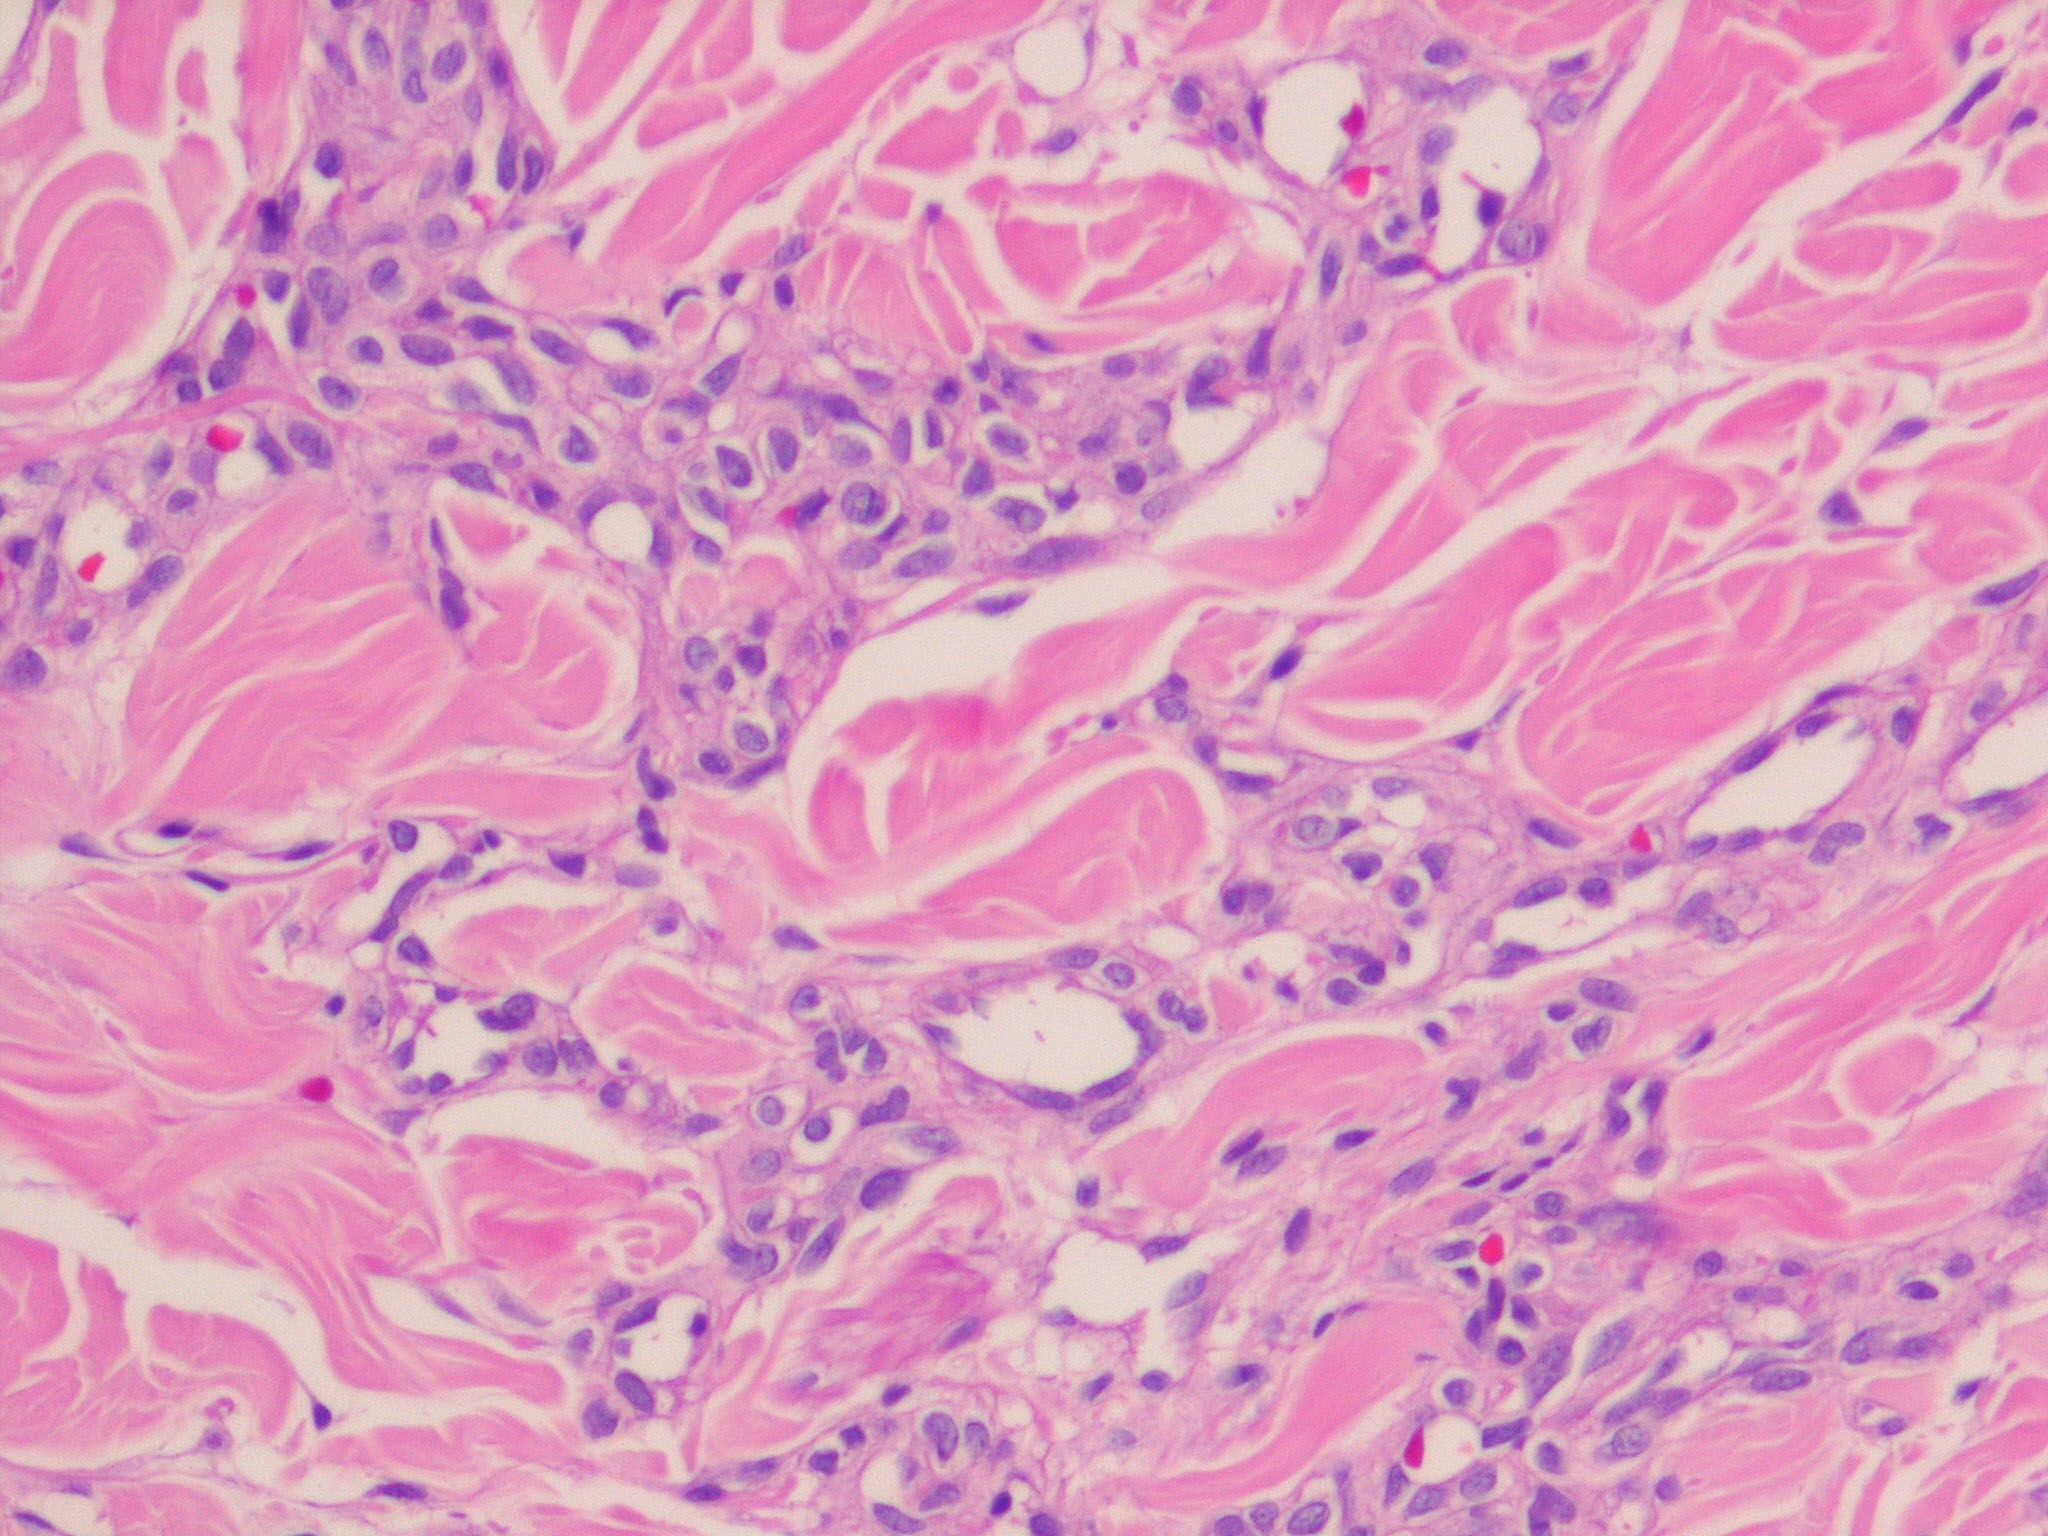

Hemangioma_microvenular = وعاؤوم الوريدات الدقيقة

OLYMPUS DIGITAL CAMERA